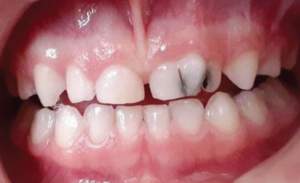

Figure 4: Image depicting primary dentition

Primary teeth are the first set of teeth in the human dentition. It comprises 20 teeth, known as primary teeth or milk teeth. Primary teeth begin to erupt in infancy and are eventually replaced by permanent teeth. Premature loss of primary teeth can result in malocclusion or crowding of the permanent successors.[11]

Primary teeth differ from permanent teeth in several anatomical and structural ways. The crowns of primary teeth are generally shorter and broader, with a thinner layer of enamel, making them more susceptible to wear. This enamel also gives them a whiter appearance compared to permanent teeth.[11] In anterior teeth, mamelons, small bumps on the incisal edge of newly erupted permanent incisors, are absent in the primary dentition. The cervical ridges are more pronounced, particularly in molars, and the crowns are more bulbous with a distinct cervical constriction.[11]

Structurally, the roots of primary teeth are thinner and more widely spread, with short or absent root trunks. These adaptations facilitate natural exfoliation as the underlying permanent teeth erupt.[11]

Functionally and morphologically, primary molars have narrower occlusal tables and flatter buccal and lingual surfaces, whereas anterior primary teeth are proportionally wider mesiodistally compared to their crown height. These distinctions are important during dental assessments and restorative procedures.[12][13]